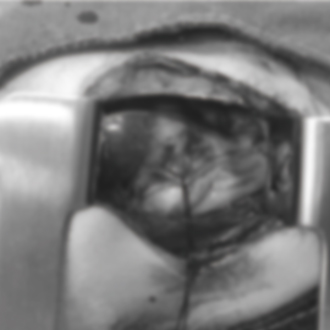

담낭점액낭종 수술

담낭에 점액이 비정상적으로 쌓여 염증이나 파열 위험이 커지는 경우에 시행하는 수술입니다.

상태에 따라 담낭을 제거해 합병증을 예방합니다.